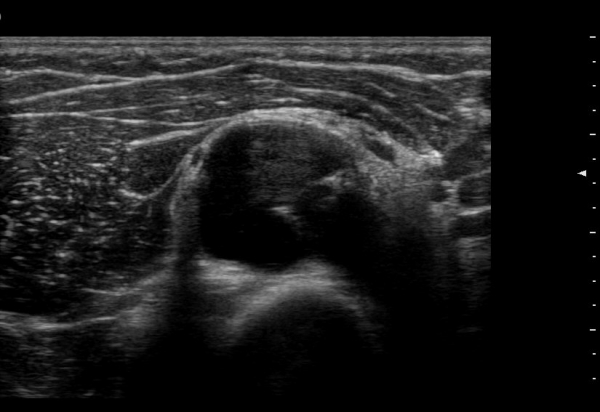

¿ä°ñ½Å°æÀÇ Èİñ°£½Å°æºÐÁö Ⱦ´Ü¸é°Ë»ç¿¡¼­ ¼ÒµÎ Ç¥Ãþ »ó¿Ï±Ù°ú »ó¿Ï¿ä°ñ±Ù »çÀÌ¿¡¼­

½Å°æ ºÐÁö°¡ Àß °üÂûµÈ´Ù(±×¸² 1).